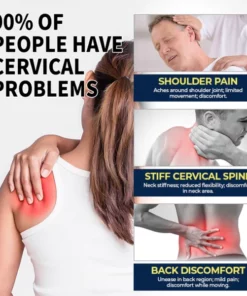

What causes cervical vertebra discomfort and Rheumatism joint pain?

If you’re feeling pain, stiffness, and limited range of motion around the neck, chances are you’re experiencing cervical vertebra discomfort. This discomfort in cervical vertebra is commonly caused by muscle tension, poor posture, herniated discs, osteoarthritis, or injury to the neck area.

The MEDix™ Contact-Free Pain Relief offers a swift, gentle, and efficient solution for individuals seeking relief from nagging shoulder pain, cervical stiffness, and bothersome back discomfort. Its efficacy lies in its ability to restore mobility and bring back the days free from pain-related concerns.